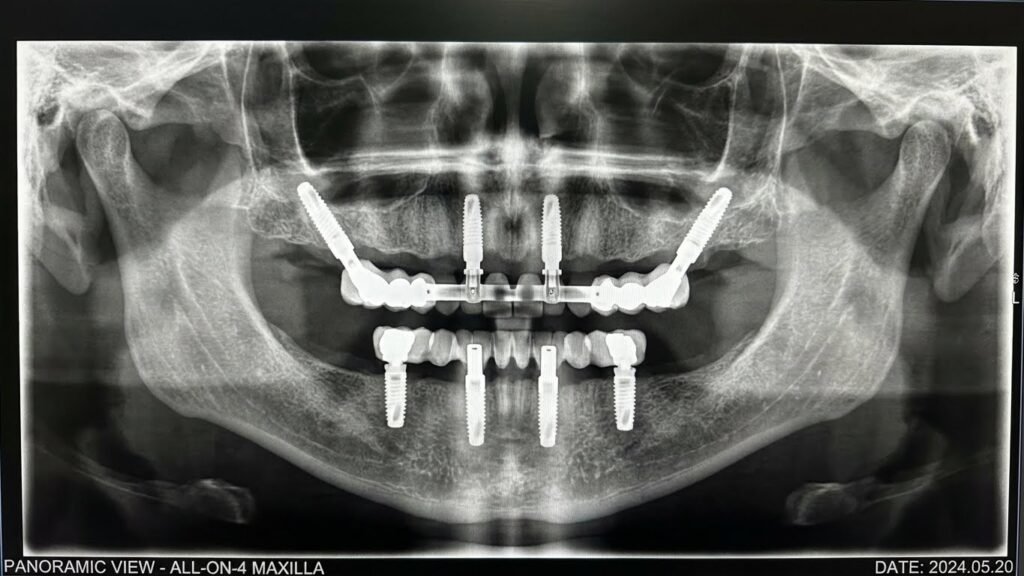

Os dois principais tipos de prótese protocolo utilizados hoje são o All-on-4 e o All-on-6. A escolha entre eles é uma decisão clínica baseada na qualidade óssea do paciente.

- Protocolo All-on-4: Utiliza 4 implantes. É a solução ideal para a maioria dos casos, especialmente quando há alguma perda óssea na região posterior, pois utiliza implantes angulados para evitar a necessidade de enxertos. Saiba mais sobre o All-on-4 aqui.

- Protocolo All-on-6: Utiliza 6 implantes. É indicado para pacientes que precisam de estabilidade máxima, como aqueles com osso de baixa qualidade (comum na maxila) ou bruxismo severo. Os dois implantes adicionais distribuem melhor as forças mastigatórias. Saiba mais sobre o All-on-6 aqui.